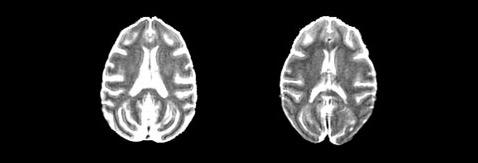

Сканирование мозга участников исследования показало, что «урезанная», но всё же полноценная по питательным веществам диета «сохраняет» больший объёма серого вещества (справа) (фото Sterling Johnson).

Неудивительно, что «худеющие» макаки-резус имели меньший вес — учёных заинтересовало другое: результаты магнитно-резонансного сканирования показали, что количество серого вещества в их мозгу превышало таковое у контрольной группы.

«Объёмы отдельных участков мозга с возрастом практически не изменились. Это явление нельзя назвать повсеместным. Однако данное открытие определённо поможет нам определить, влияет ли диета на потерю нейронов», — поясняет нейробиолог Стирлинг Джонсон (Sterling Johnson).

Несмотря на то что нетронутыми оказались области, отвечающие за регуляцию движений, а также за память и решение определённых задач, американцы пока не могут сделать выводы о последствиях такого различия. Дело в том, что они ещё не сравнивали познавательные способности выживших животных.

«На данный момент мы можем говорить лишь о наблюдаемых различиях объёма участков мозга, вероятно, связанных с рационом питания», — добавляет Джонсон.